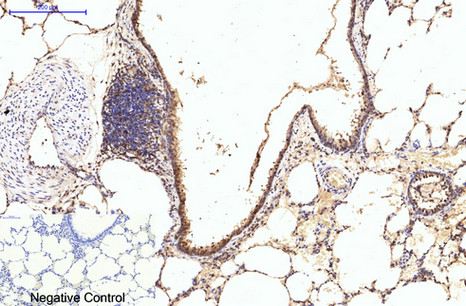

Immunohistochemical analysis of paraffin-embedded Rat-lung tissue.